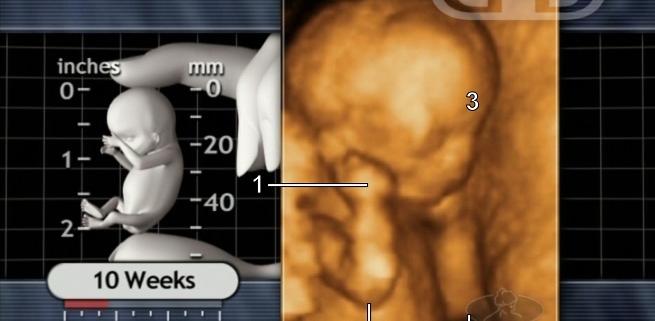

Here is an ultrasound picture of a baby at ten weeks after conception from the Endowment for Human Development.

At this stage, a preborn baby has had a beating heart for seven weeks. The baby has a brain that is giving off waves. He or she shows a startle reaction if touched by something. The baby can have the hiccups.

A 10-week-old preborn baby is already right or left handed. If biologically female, she has ovaries and a uterus of her own. He or she not only has hands and fingers, but also fingerprints.

“Something recognizable” hardly covers it.